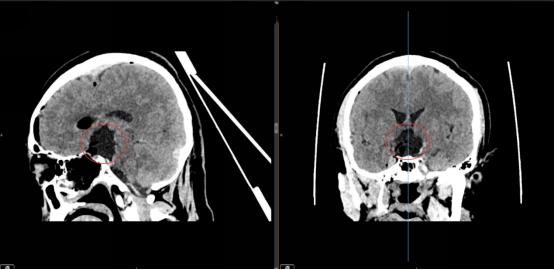

手术团队借助内镜高清放大的视野优势,如同拥有了“透视眼”,清晰捕捉到肿瘤与周围血管、神经的每一处细微关联,细致分离肿瘤与重要组织粘连,一点点剥离、精准切除病灶,既确保肿瘤被完整切除,又最大限度保护了正常脑组织及神经功能,成功规避了术中副损伤的风险。

(图为术后影像)